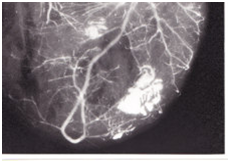

2 pts (4.3%) Table 2 showed sudden H as a symptom of impending rupture (respectively from 118/86 mmHg to 180/95 mmHg and 145/90 mmHg to 190/98 mmHg) and chest pain resistant to opiates. They deceased within 1 hour from increased H. The other 44 pts with PCR were hypertensive in 27 cases (61%) at the admission, while 17 (39%) displayed no H. Pts with rupture (Figures 1-4), and (Table 3) had a statistically significant number of multiple coronary alterations, cardiac hypertrophy (mean heart weight 627+/-188 grams and left ventricle wall thickness 25+/-3 mm vs 400+/-75 grams for heart weight and 14+/-2mm for left ventricle wall thickness in pts with no rupture), irregular areas of confluent fibrosis and coronary narrowing up to 90% with a high incidence of occlusive thrombi.

Figure 1 Postmortem angiography of heart with post infarction rupture. It can be seen an irregular filling of the coronary tree and a large a vascular area at the site of the infarction.